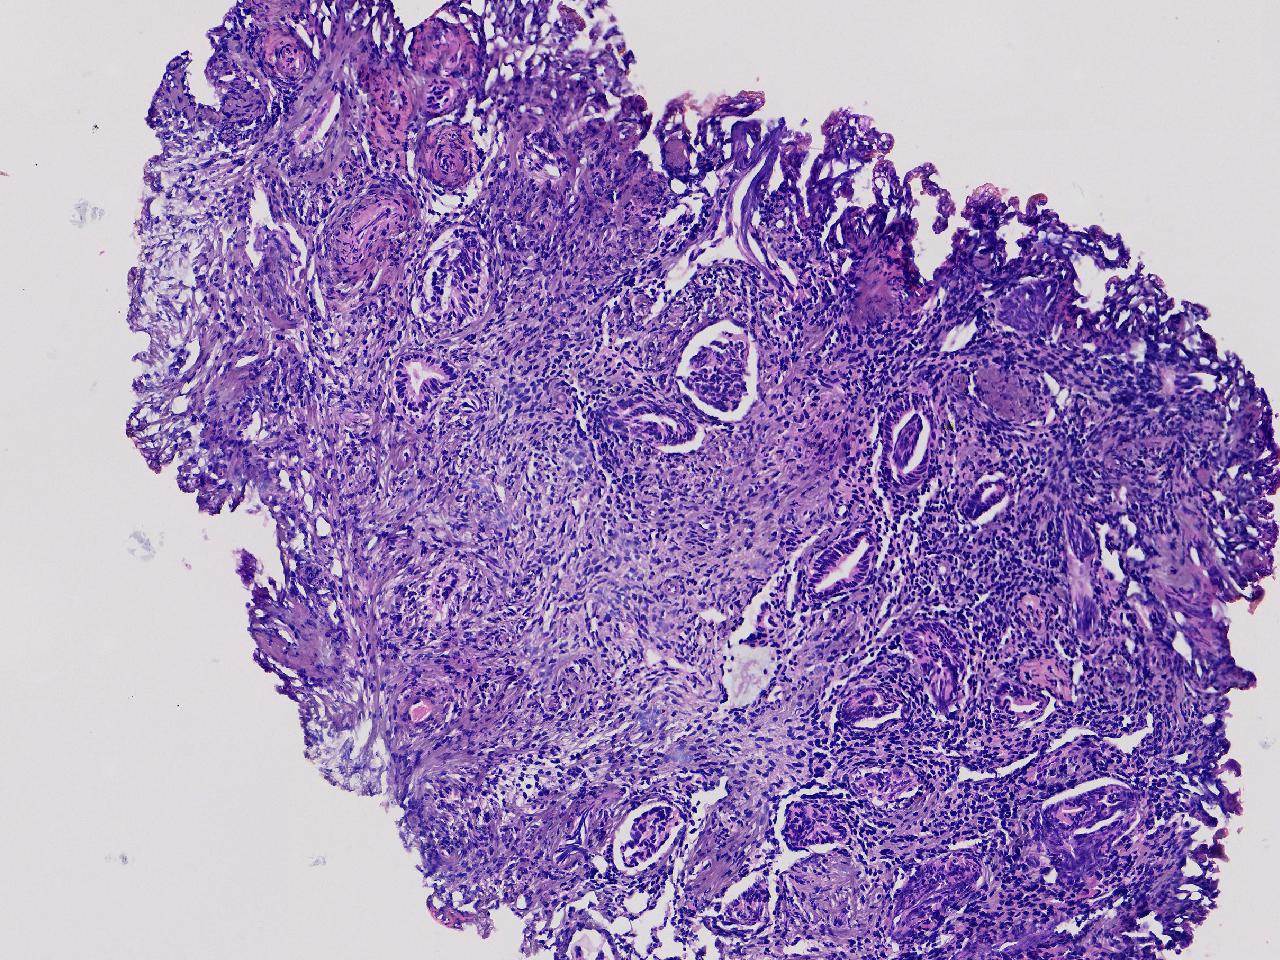

宫腔息肉?

性别

女

年龄

56岁

彩超示宫腔内见5x3ml的团状偏强回声结节,边界清。

灰粉色不整形软组织多块,0.5X0.3X0.3厘米。

首先考虑子宫内膜息肉,有些区域间质细胞较密,找找看有没有核分裂。

彩超提示强声团体积不小,待完整切除送检再综合诊断。